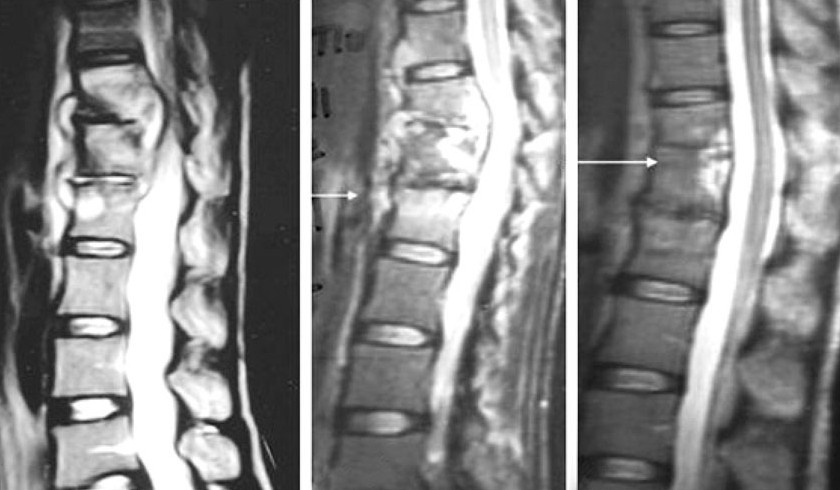

化膿性脊椎炎(かのうせいせきついえん)

脊椎に細菌が侵入して炎症を起こし膿がたまる病気。

脊椎カリエス(結核性脊椎炎)

肺からの結核菌(けっかくきん)が血行性に運ばれて発症する結核性脊椎炎です

脊髄腫瘍・脊椎腫瘍

脊髄(中枢神経)や脊椎(背骨)やにできる、良性または悪性の腫瘍